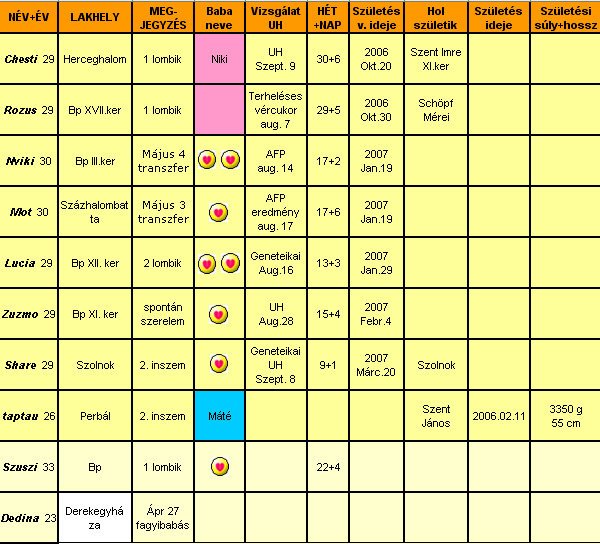

Sziasztok!

Chesti, vettetek már babakocsit? Még mindig akciósnak láttam azt a Pierre Cardint, amiről beszéltél.

Zuzmo, csodálatos élmény lehetett az UH.

Kicsit irígy-irígy.... Meddig dolgozol még?

Rozus, nagyon jók a képek.

Nevetek van már? (lehet, lemaradtam róla)

Viki, le a kalappal, hogy eddig bírtad. Most már tessék sokat pihenni. Brendonban nézelődni jó, és ötleteket szerezni.

Aztán máshol megveszed olcsóbban, vagy elkészítitek saját kezűleg (pl. ágynemű, baldachin, falvédő, stb.).

Lucia, örülök, hogy róka koma elpártolt tőled. Véredet rendszeresen nézik? Ugye neked csak fekvéskor kell majd véralvadásgátlót használnod?

Taptau, jó tanácsokat írsz, mint tapasztalt anyuka. Örülök neki. Homeopátia ügyben, lehet zaklatni foglak. Érdekel a téma, és szeretnék személyes benyomásokról hallani.

Lányok-fiúk, annyira szuper eredmények születnek. Ebből is látszik, hogy a mesterséges megtermékenyítés nem jelenti azt, hogy valami nem stimmel a gyerekkel, más lenne. Sajnos az a tapasztalatom, hogy, ha szóba kerül az inszem-lombik, az emberek a nagy tudatlanságban sok hülyeséget képesek gondolni. És hiába magyaráznám el, nem is hallgatják meg. Rossz sztereotípiák, nem is akarnak tudni arról, hogy másképp is lehet. Nem szeretnék általánosítani, de a többség sajnos ilyen (még szomorúbb, hogy tanult, intelligens embertársaink is kőkeményen tartják magukat ahhoz, hogy lombikkal "hülyegyerekek" születnek - bocsi, nem én mondtam). Saját családi példa, amikor úgy döntöttünk, nem mondjuk, hogy a inszemmel fogant (ha szóba kerül nem tagadjuk, de nem "reklámozzuk). Férjem mamája tudta, hogy szeretnénk már nagyon babát (9 éve vagyunk házasok, ő már akkor dédunokát várt). 1-2 szóval néha elmondtuk, hogy gyógyszert szedek, szurit kapok, később Bp-re járunk orvoshoz. Amikor sikerült, nagyon örült. Láttuk, hogy valamit nagyon akar kérdezni, csak kinyögte, hogy ugye nem lombik volt? Mondtuk hogy nem, hát láttátok volna azt a megkönnyebbülést. Inkább bele sem mentünk az inszembe. Igaz, ő már idős néni, de sajnos a kétgyerekes, okos barátnőm ugyanígy reagált. Ti hogyan látjátok?

Voltam védőnőnél.

Két hét alatt 1,5 kg-ot híztam (a sok sajtos kenyér, amin éltem). Most már oda kell figyelnem, ha nem akarok bálna lenni. Vérnyomásom 90/50. Ne csodálkozzak, hogy szédelgek és húz az ágy. Nem tudom mi legyen, mert rendszeresen kávézni-teázni nem akarok elkezdeni.

Pisilni még mindig 1x kelek fel éjszaka. Ez most akkor sűrűsödni fog?

A legújabb, hogy alul fájdogál a hasam. Nem éles fájdalom, inkább csak érzem. Holnap megyek haematológushoz, lehet, hogy bekönyörgöm magam egy Uh-ra, ha elérem a dokimat. Nem bírom ki jövő hét péntekig.

Na, jó. Kibírom, de nehezen.

Húú, jó sokat írtam. Így jár, aki csavarog.

Csatolok egy képet. Az eddigi szuritermésem. Tegnap leadtam a háziorvosomnak. Benne van a 2. inszemből is 1-2 tű + a véralvadásgátlók.

Szép napot mindenkinek!